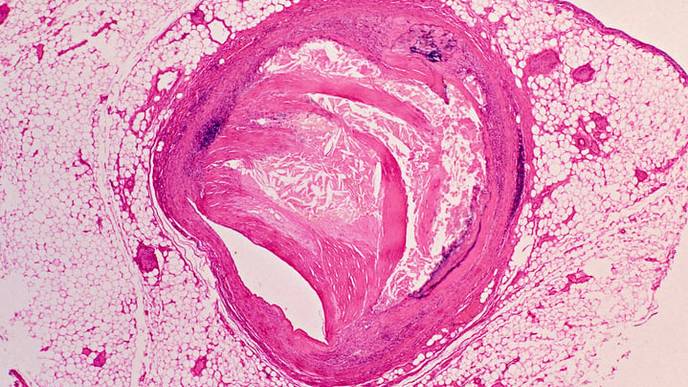

January 31, 2024 — Coronary artery calcification is increasing in prevalence, leading to greater risks both during procedures such as percutaneous coronary intervention (PCI) and adverse events in the short and long term. Along with these challenges, treatment options are expanding, increasingly including calcium modification prior to stent implantation. A newly published SCAI Expert Consensus Statement on the Management of Calcified Coronary Lesions outlines methods for interventional cardiologists to identify various types of calcified coronary lesions and presents an algorithm to help them guide the use of these various calcium modification strategies.

- Calcified coronary lesions are becoming commonplace in the cardiac catheterization lab, and their treatment is associated with increased short- and long-term risks compared to noncalcified lesions.

- The use of intravascular imaging and the proper use of calcium modification devices can help decrease these risks.